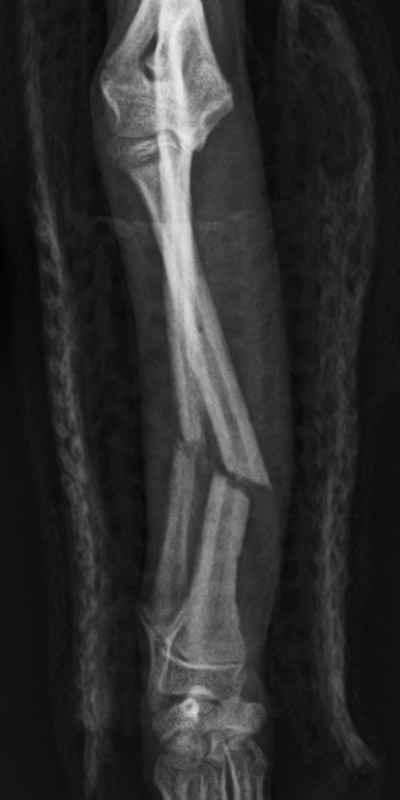

橈尺骨骨折

トイプードル(8カ月齢)

ボール運動中に転倒

手術前